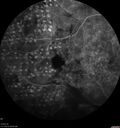

PDR and Vitreous hemorrhage - Second FA is following PRP laser266 views42 year old man (date 2018): Prior to 2 months ago the vision in the right eye was good. This started with a glob in the vision and then the vision got better. Then the string came back down and is getting bigger and bigger. The last time he had bleeding in the left eye he had surgery in 2009. The left eye is now doing OK other than there is a cataract. The right eye had some laser treatment done in 2009. The vitrectomy and laser were done at William Beaumont.

VA OD: sc3'/200 NscUnable

VA OS: sc20/40 NscJ2-1